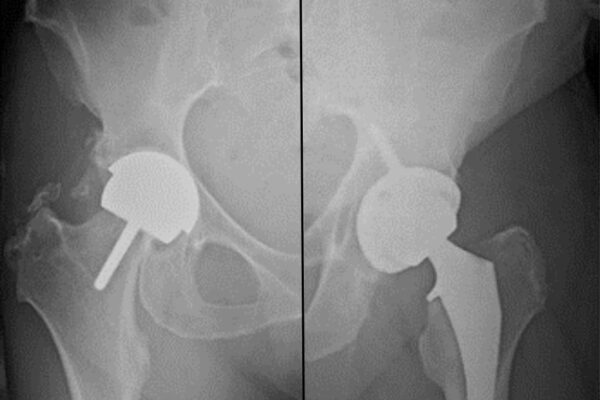

Hip pain can severely affect daily life. Walking, exercising, or even sitting for long periods becomes a struggle when arthritis or joint damage sets in. For many patients, surgery becomes the best option to restore mobility and reduce pain. Two procedures are commonly discussed hip resurfacing and hip replacement. While both aim to relieve discomfort…